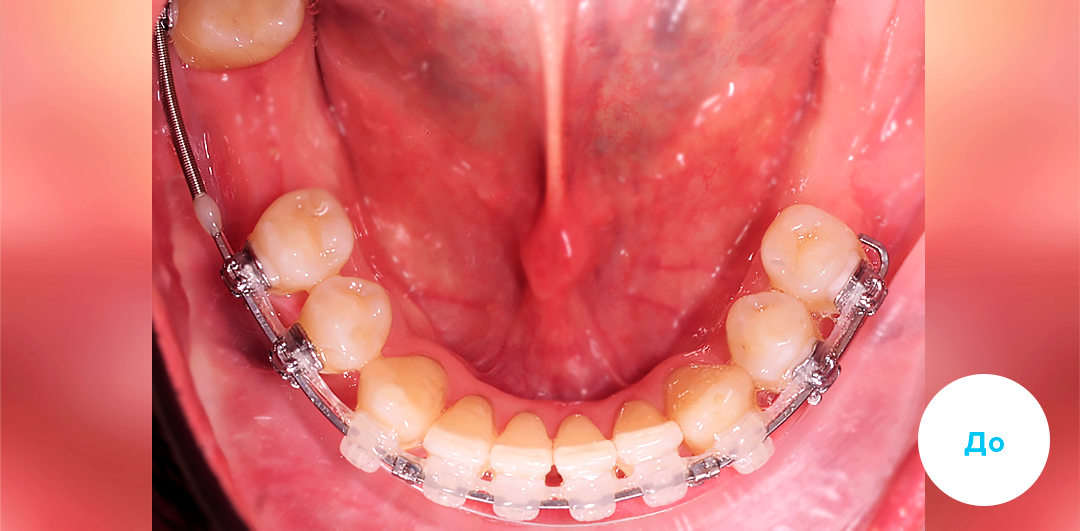

Результаты лечения